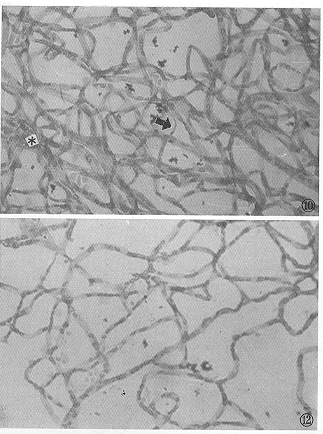

图1 正常组大鼠视网膜膜盘结构清晰,排列规则 ×15000 图2 正常组大鼠视网膜毛细血管。E为内皮细胞核,P为周细胞,BM为基底膜,L为毛细血管管腔 ×6000 图3 造模组大鼠视网膜膜盘排列紊乱,结构溶解破坏 ×15000 图4 造模组大鼠视网膜毛细血管基底膜电子密度不均匀,结节样增厚(黑箭头),胞质内线粒体肿胀(△),有吞饮小泡增多现象(白箭头)×12000 图5 治疗组视网膜膜盘排列较乱,结构模糊 ×10000 图6 治疗组视网膜毛细血管基底膜电子密度不均匀,结节样增厚(黑箭头),胞质内部分线粒体肿胀变性,无吞饮小泡增多现象,R为红细胞 ×15000 图7 预防组视网膜膜盘排列稍乱,结构尚清晰 ×15000 图8 预防组视网膜毛细血管基底膜电子密度不均匀,无结节样增厚现象,线粒体结构基本正常(黑箭头),无吞饮小泡增多现象 ×10000 图9 正常大鼠视网膜血管结构 消化铺片 HE ×100 图10 造模组大鼠视网膜毛细血管排列紊乱,迂曲交叉,有的扭曲成团,管经不规则,粗细不均,出现无细胞毛细血管(黑箭头),可见微血管瘤(*)消化铺片 HE ×200 图11 治疗组大鼠视网膜毛细血管管腔不规则,动静脉排列稍乱,迂曲交叉,但较造模组病变轻,未见无细胞毛细血管。偶可见毛细血管瘤(*)消化铺片 HE ×400 图12 预防组大鼠视网膜毛细血管管腔基本规则,无明显动静脉迂曲交叉现象,无毛细血管瘤和无细胞毛细血管 消化铺片 HE ×200